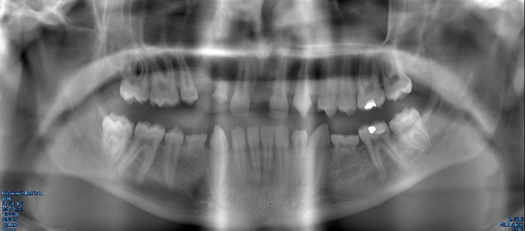

Fig 7. Panoramic radiograph, 14-year-old brother.

Figure 7

Figure 5 through Figure 12 exemplify what currently may present in private dental practices with these types of patients. Four brothers aged 14 years to 27 years all suffered from obstructed airways; high incidence of caries of dentin, enamel, and cementum; moderate periodontal disease; collapsed vertical; undiagnosed OSA; and the potential for increase in comorbidities such as diabetes, cardiovascular disease, dementia, cancer, high blood pressure, and others. Symptomology was presented throughout the young lives of the brothers in this family. The parents were unaware that the dental agenesis and premature permanent tooth extraction could have led their sons into severe health issues as they matured.